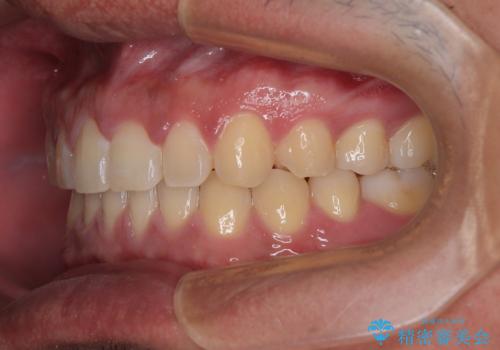

- 上下前歯の隙間を気にして来院された患者様です。

飲み込みや話をするときに舌を突出させる癖が強くあり、それが原因でスペースが空いていました。

舌癖を改善するためのトレーニングを行いながら、ワイヤー装置を用いて前歯の隙間を閉じていくこととしました。

舌のトレーニングをしっかりと行ってくださったおかげで、順調に治療を終えることができました。

舌の突出癖が速やかに改善され、後戻りによるスペースは今のところ認められておりません。